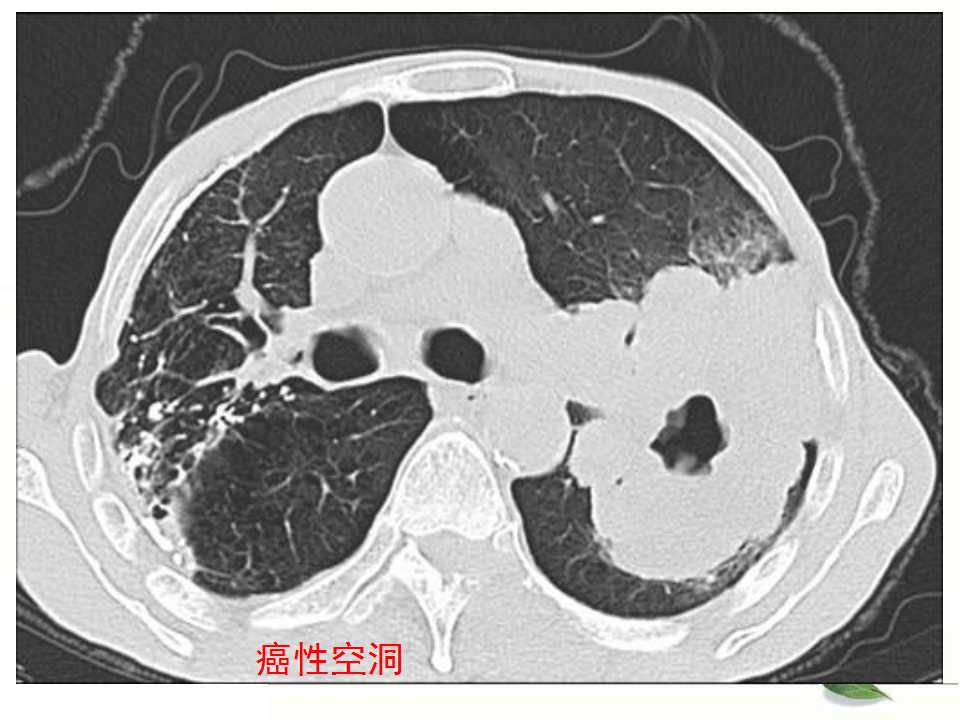

肺癌的影像学检查